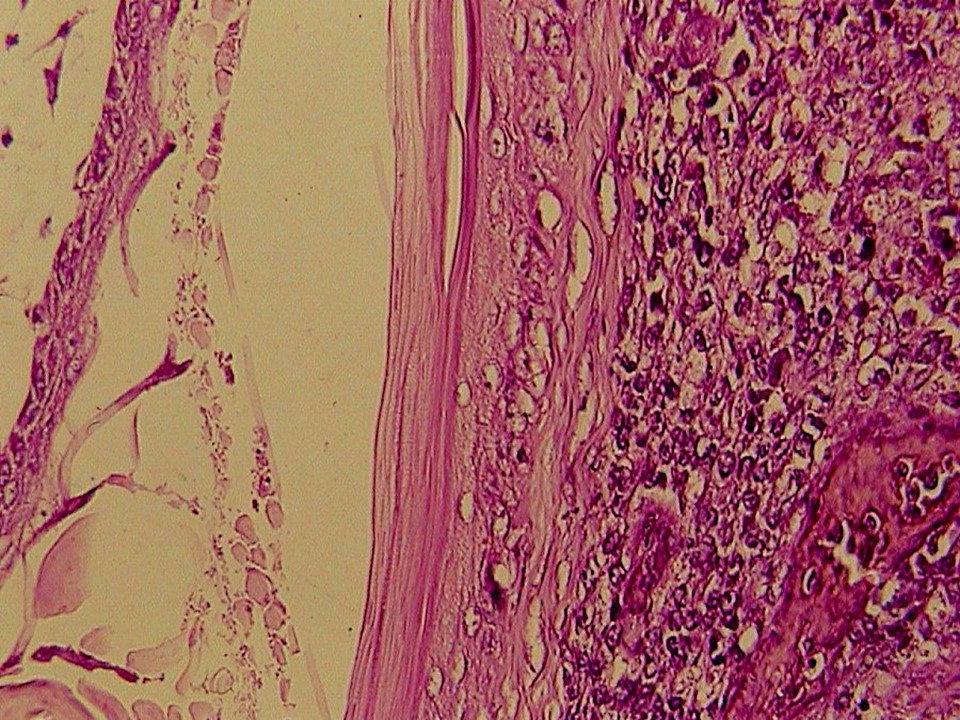

疾病中文名稱:馬立克病

疾病英文名稱:Marek's disease

作者:蔡信雄教授